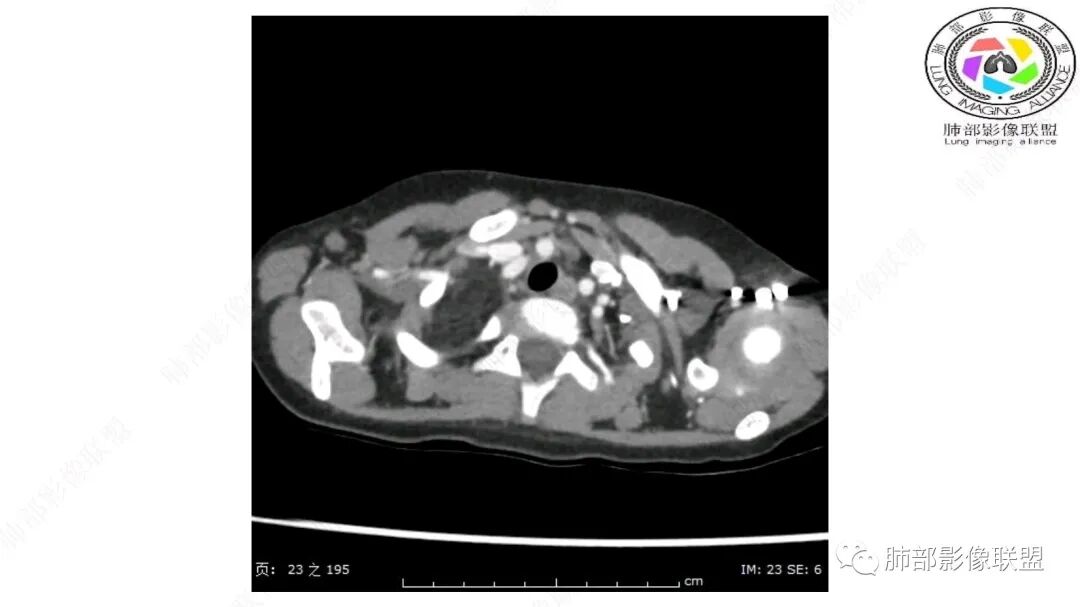

跨肺门,包绕肺血管分支,邻近肺组织受压肺不张。

可以看到造影剂进入的丛状结构

密度不均,非纯脂肪成分。斑片状密度略高区域有轻度填充式强化。

婴幼儿,病变较大,跨肺门,分叶,富含纤维或黏液、含成熟脂肪,破坏力弱或无,浸润性生长模式不明显,未见远处转移。

综合:富含成熟脂肪的、可以有丛状结构的,可以有纤维或黏液的良性或低度恶性肿瘤。常见疾病谱:脂肪瘤、神经纤维瘤样错构瘤、冬眠瘤、血管脂肪瘤、髓脂肪瘤、脂肪母细胞瘤、黏液样脂肪肉瘤。

鉴别要点:病变成分不单一,非包绕神经结构、间质血管不显著、婴幼儿,良性或低度恶性。